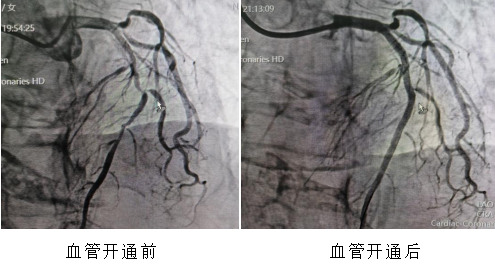

这不是一组普通的时间记录,而是一个真实的、发生在海南医科大学第一附属医院导管室的急救故事——前不久的一天,12小时内,通过胸痛中心绿色通道,5位急性心肌梗死患者,5台急诊经皮冠状动脉介入治疗(PCI)手术,全部成功。

22分钟、70分钟、36分钟、18分钟、12分钟——这是5颗心脏血管从“断流”到“复流”,解除堵塞病变的时间。如此高密度、高效率的连续急救,绝非偶然,它是我院胸痛中心标准化、流程化救治能力的集中体现。它的背后,是院前院内无缝联动,120急救车上已完成的心电图传输与初步诊断,患者“未到,信息已到”,导管室提前启动;是术前早已启动的医院胸痛中心绿色通道——患者到我院后可绕行ccu和(或)急诊科,直接进入导管室,最大限度压缩术前准备时间;更是心内科、急诊科、心电图室、导管室护理团队等多学科团队的无缝咬合,高效协作。这是急诊急救体系建设的力量。